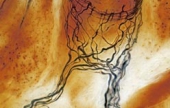

Levenhuk 870T — надежный тринокулярный биологический микроскоп, с помощью которого производится весь спектр наблюдений как в светлом, так и в темном поле. Широко используется в медучреждениях разного типа для урологических, дерматологических, биологических, биохимических, патологоанатомических, цитологических, гематологических и общеклинических лабораторных исследований. А поскольку это тринокуляр, то в комплекте с камерой-окуляром его можно без проблем использовать в качестве цифрового микроскопа. Цена: 650 000 тг. |